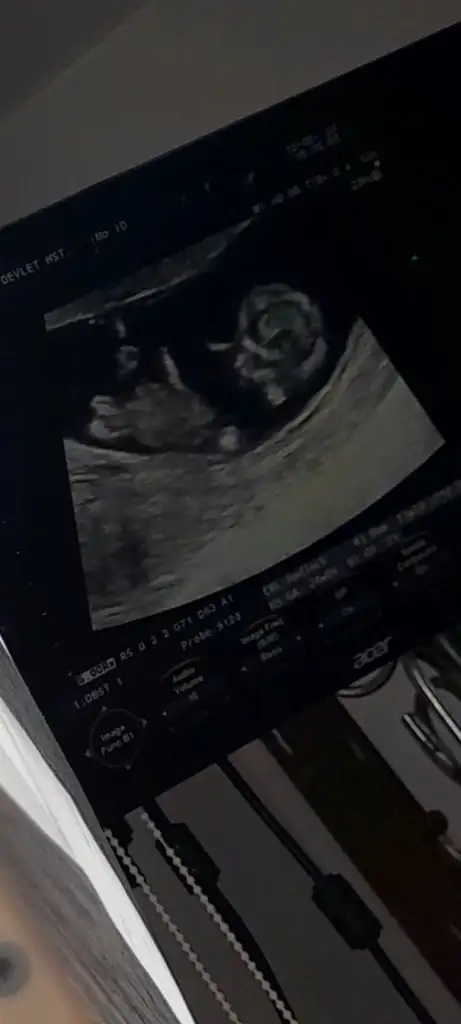

Bizde bugün 11+4 olmuşuz regle göre 2 3 gün gerideydik yakalamışız çok şükür kalp atışı 168, ense burun vs iyi dedi doktorum cinsiyet yorumu yapmadı salı günü nipt cikacak umarım sağlıklıdır bebeğim yüz ustu yatıyordu ve uyuyordu çok bir şey anlamadım ben o yüzden bazı ilaçlara başladı folik asit elinde ki bitsin bırak dedi, 1 kilo vermişim bu aylarda vermenin çokta önemli olmadığını söyledi bilginiz olsun, sağlıklı hayırlı evlatlar imiz olsun inşallah